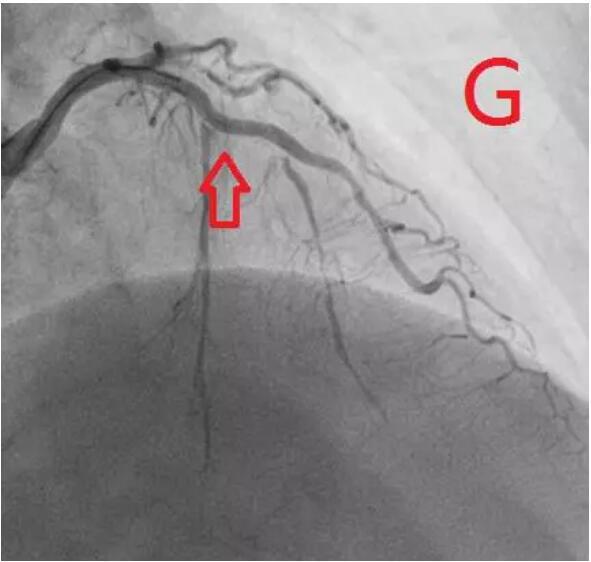

对冠状动脉造影及IVUS图像进行综合判断,目前已经具备安全进行冠状动脉支架治疗的条件,于是在病变处植入支架治疗,随后在IVUS指导下采用后扩球囊改善贴壁情况,顺利完成手术(图G、H)。